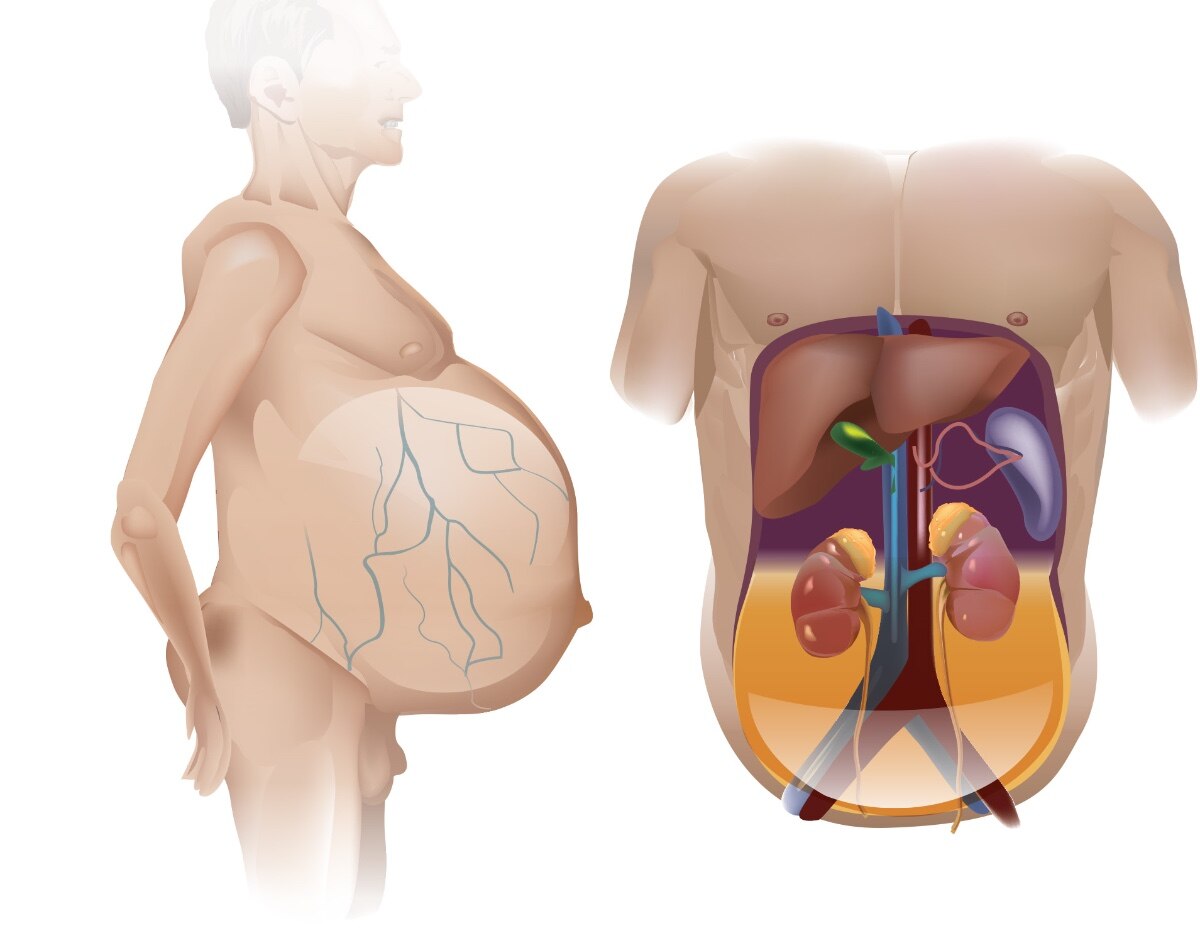

A hiatal hernia occurs for many reasons but is most often due to unrelated medical conditions and predisposing factors. Risk factors for hiatal hernia include a history of multiple pregnancies, skeletal disorders with bone decalcification and degeneration, chronic constipation, and chronic obstructive pulmonary disease (COPD). Because of increased muscle weakness and decreased elasticity, it is estimated that 55% to 60% of people over the age of 50 years old have a hiatal hernia. Hiatal hernia is estimated to occur in approximately 94% of clients who have GERD and is present in roughly 40% of clients who are morbidly obese. In addition, there is a greater prevalence in clients who are pregnant or after pregnancy due to the increased intra-abdominal pressure attributed to the enlarged uterus.